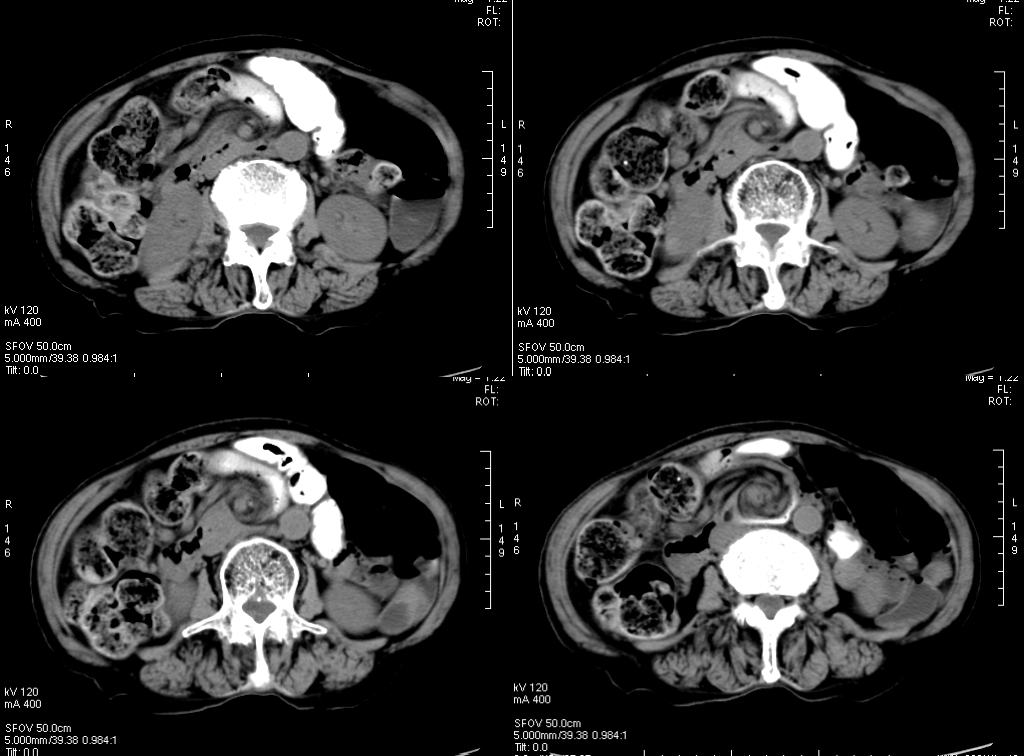

3、不成比例脂肪绞缠征

不成比例脂肪绞缠主要指的是增厚肠壁和周围脂肪在数量方面比例的严重失衡。在少数急性胃肠道疾病中,以肠壁相邻的肠系膜为中心而不是以肠壁为中心,因此肠壁周围脂肪增厚明显高于肠壁厚度。和这一征像相关的疾病主要包括4类:憩室炎、肠脂垂炎、网膜梗死和阑尾炎。胃肠道的大多数炎性疾病包括感染性的、非感染性的和局部缺血性的病变,都是以肠道为中心。这些疾病的肠壁增厚程度往往超过相邻脂肪条索的厚度。但是对于少数以肠壁临近系膜为中心的疾病,脂肪增生明显超过肠壁的厚度。

左上图:右侧腹横肌深面、胆囊内前方梭形囊性病变,有壁但不均匀,略有强化。与腹横肌成锐角,腹横肌肥厚。周围脂肪模糊,有索条点状影。

右上图:邻近降结肠远端系膜壁旁可见一卵圆形类似脂肪密度的病变,周边可见火焰样炎性改变,邻近肠壁有轻微增厚,无明显脓肿及肠梗阻征象。

左下图:肠壁增厚,结肠袋襞显影不良,以及结肠周围脂肪束条状改变。

右下图:CT显示壁明显增强的管状结构(箭头),右中腹的脂肪系膜反应。